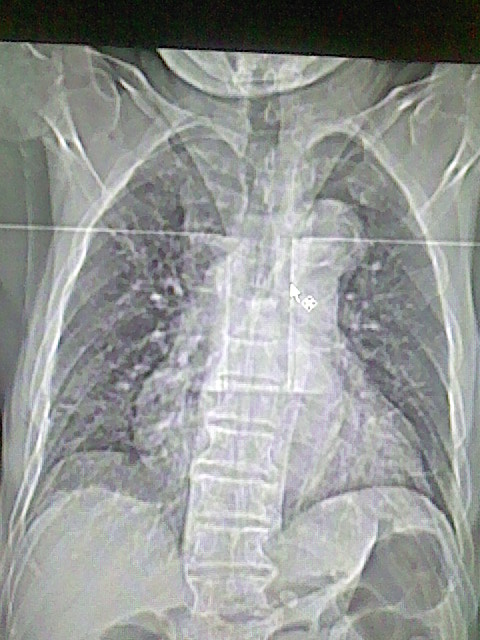

以下是引用zsl6918在2008-8-28 16:49:00的发言:[br]双肺炎性病灶,食管狭窄估计与心房增大压迫所致。

以下是引用xulianj在2008-8-28 20:36:00的发言:[br]慢支肺气肿伴感染,右上肺陈旧性结核;食道建议胃镜检查。

以下是引用wqs571018在2008-8-28 21:18:00的发言:[br]慢支继发感染,右上肺陈旧性结核;食道建议胃镜检查。